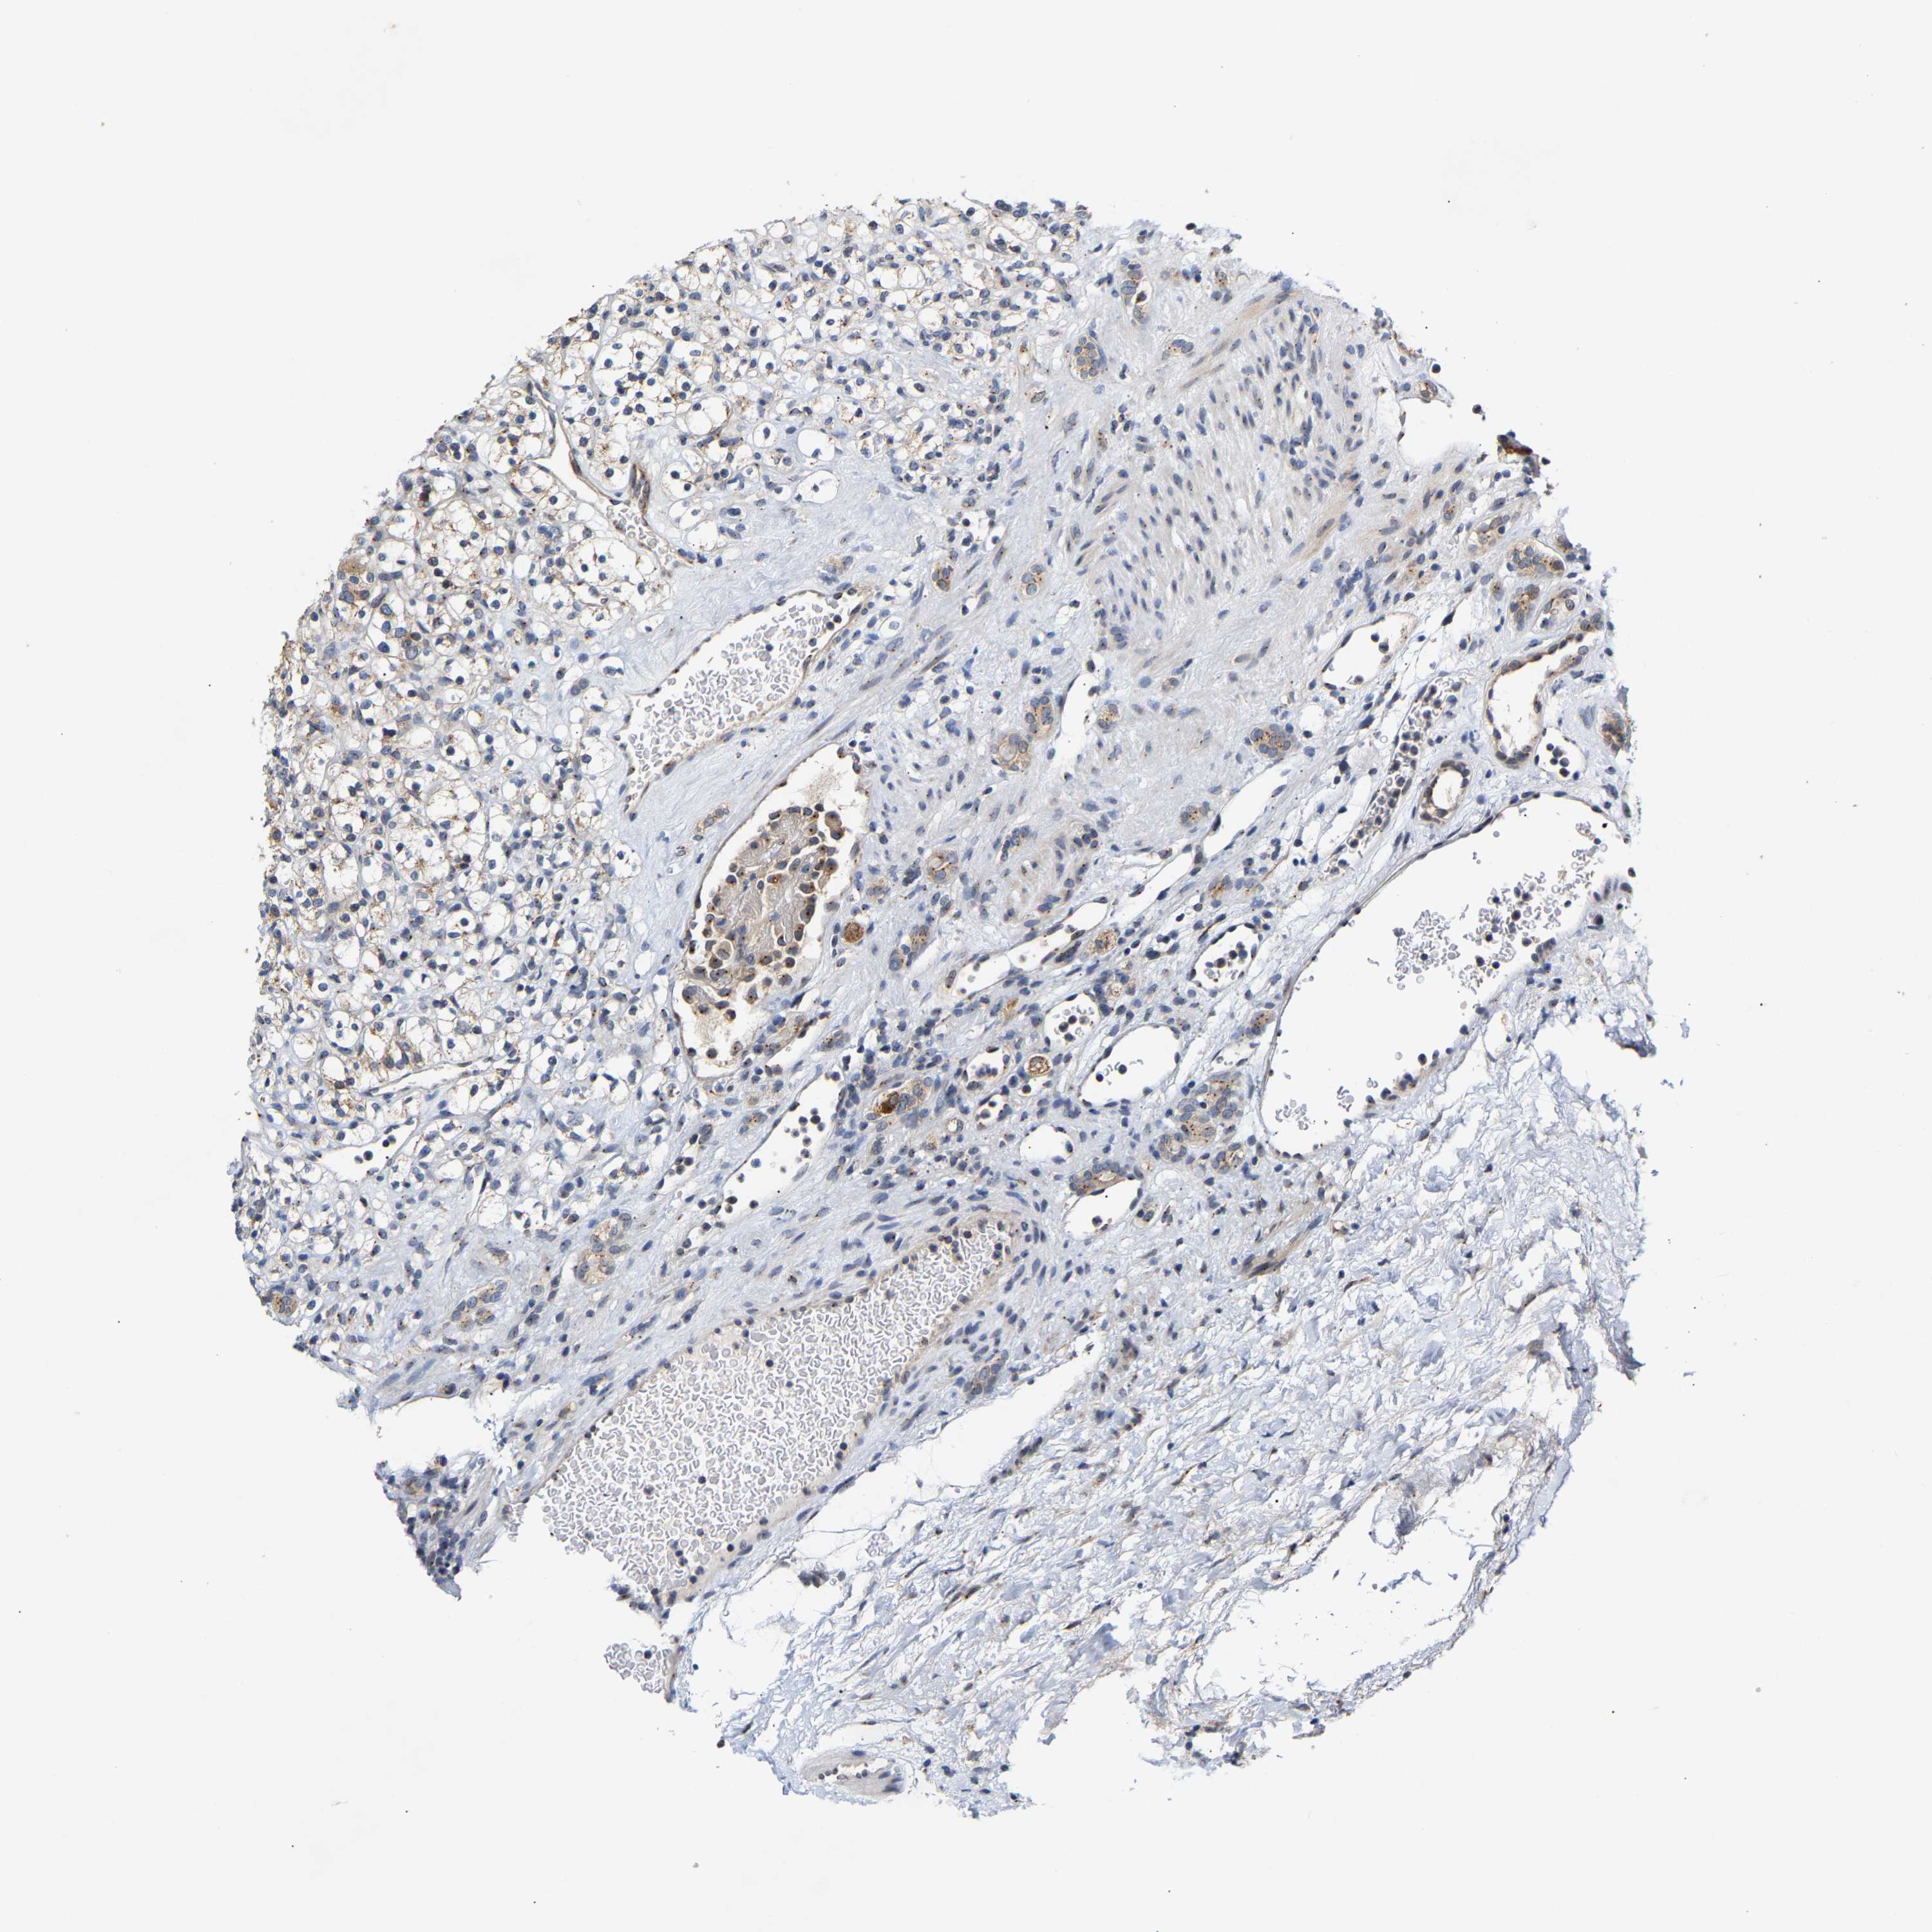

KIDNEY RENAL CLEAR CELL CARCINOMA (VALIDATION) - Interactive survival scatter ploti

The Survival Scatter plot shows the clinical status (i.e. dead or alive) for all individuals in the patient cohort, based on the same data that underlies the corresponding Kaplan-Meier plots. Patients that are alive at last time for follow-up are shown in blue and patients who have died during the study are shown in red.

The x-axis shows the expression levels (FPKM) of the investigated gene in the tumor tissue at the time of diagnosis. The y-axis shows the follow-up time after diagnosis (years). Both axes are complimented with kernel density curves demonstrating the data density over the axes. The top density plot shows the expression levels (FPKM) distribution among dead (red) and alive patients (blue). The right density plot shows the data density of the survived years of dead patients with high and low expression levels respectively, stratified using the cutoff indicated by the vertical dashed line through the Survival Scatter plot. This cutoff is automatically defined based on the FPKM cutoff that minimizes the p-score. The cutoff can be changed by dragging the vertical line or by entering a cutoff value in the square labeled "Current cut-off".

Under the Survival Scatter plot the p-score landscape (black curve; left axis) is shown together with dead median separation (red curve; right axis). Dead median separation is the difference in median mRNA expression between patients who have died with high and low expression, respectively. It is calculated as follows: median FPKM expression of dead patients with high expression - median FPKM expression of dead patients with low expression. This is intended to aid the user in visually exploring custom cutoffs and the associated p-scores and dead median separation.

Individual patient data is displayed and can be filtered by clicking on one or more of the category buttons on the top of the page. Categories describing expression level and patient information include: high, low, alive, dead, female, male and tumor stages. The scale of the x-axis can be toggled between linear and log-scale by clicking on the "x log" button. Mouse-over function shows TCGA ID, patient information and mRNA expression (FPKM) for each patient.

& Survival analysisi

Kaplan-Meier plots summarize results from analysis of correlation between mRNA expression level and patient survival. Patients were divided based on level of expression into one of the two groups "low" (under cut off) or "high" (over cut off). X-axis shows time for survival (years) and y-axis shows the probability of survival, where 1.0 corresponds to 100 percent.

PCNT is not prognostic in Kidney Renal Clear Cell Carcinoma (validation)

Best expression cut offi

Based on the FPKM value of each gene, patients were classified into two groups and association between prognosis (survival) and gene expression (FPKM) was examined. The best expression cut-off refers the FPKM value that yields maximal difference with regard to survival between the two groups at the lowest log-rank P-value. Best expression cut-off was selected based on survival analysis .

When clicking on this number, the vertical dashed line indicating cut-off, the interactive survival plot, and the Kaplan-Meier curve will be adjusted to show results based on the best expression cut-off.

: 5.35

P scorei

Log-rank P value for Kaplan-Meier plot showing results from analysis of correlation between mRNA expression level and patient survival.

N/A

TCGA RNA samplesi

RNA-seq data is reported as average FPKM (number Fragments Per Kilobase of exon per Million reads), generated by the The Cancer Genome Atlas (TCGA) .

Normal distribution across the dataset is visualized with box plots, shown as median and 25th and 75th percentiles. Points are displayed as outliers if they are above or below 1.5 times the interquartile range. FPKM values of the individual samples are presented next to the box plot.

Average pTPM 5.6

Number of samples 100